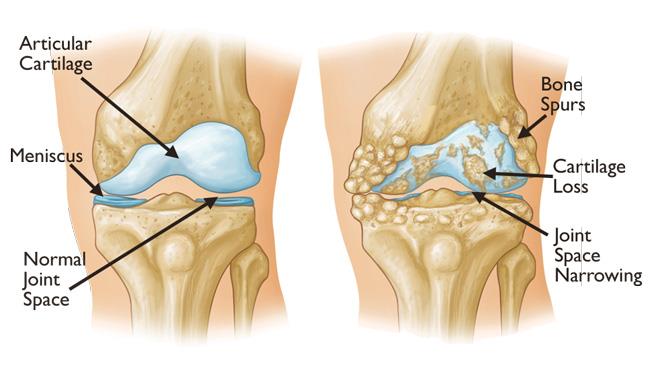

رایج ترین دلیل که منجر به جراحی آرتروپلاستی می شود ، آسیب مفصلی به دلیل آرتریت است .انواع مختلفی از آرتریت وجود دارد که می تواند این مشکل را ایجاد کند. مانند استئوآرتریت ، آرتریت روماتوئید و آرتریت ناشی از ضربه که به دلیل وارد شدن ضربه به زانو ایجاد می شود. آرترزو معمولا به دلیل افزایش سن و فرسایش مفصل زانو ایجاد می شود. آرتریت روماتوئید نیز نوعی بیماری خود ایمنی است که مفصل زلالهای (سینوویال) را ملتهب می کند.این التهاب مزمن می تواند به مرور زمان به غضروف آسیب وارد کرده و در نهایت باعث از بین رفتن غضروف شود.آرتریت روماتوئید شایع ترین نوع از گروه اختلالات آرتریت التهابی است . تفاوت مفصل سالم (سمت چپ) با مفصل آسیب دیده (سمت راست) تفاوت مفصل سالم (سمت چپ) با مفصل آسیب دیده (سمت راست)